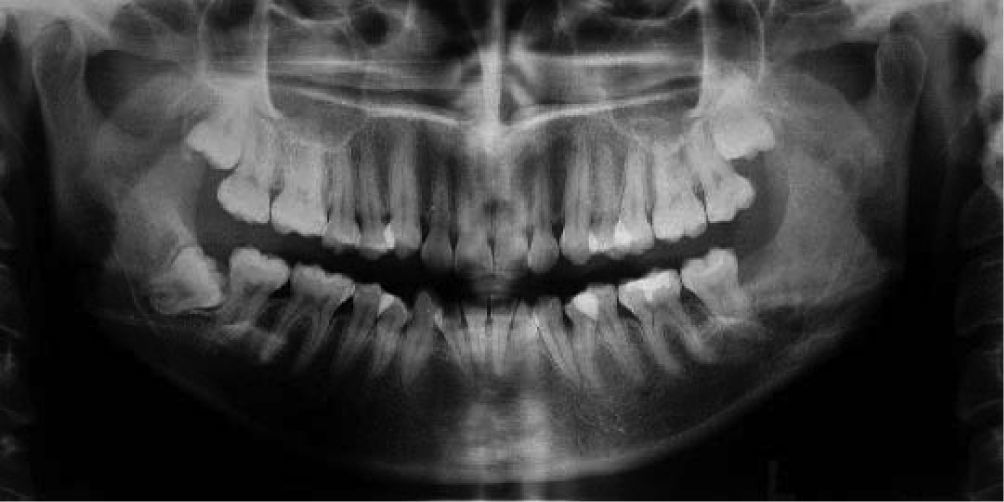

Con la hipótesis diagnóstica de quiste mandibular odontogénico o tumor odontogénico se solicita estudio imagenológico previo a biopsia. La radiografía panorámica revela una extensa lesión radiolúcida de límites netos, uniloculada y que compromete la totalidad de la rama ascendente mandibular. Asociada a la lesión, se observa el tercer molar incluido en posición baja y en distoversión (fig. 2).